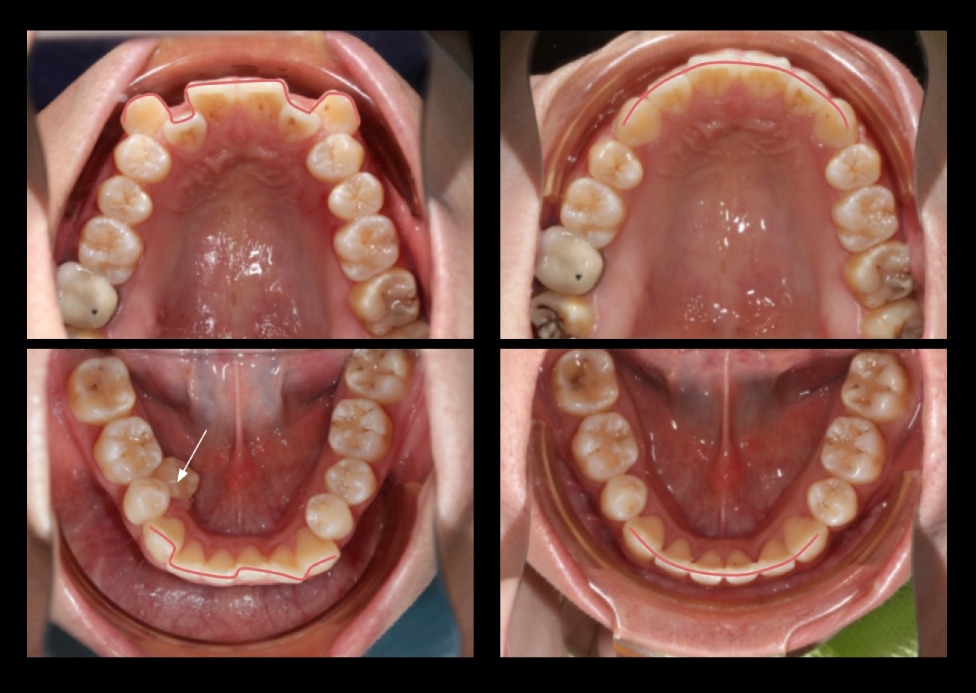

Case 5. 嘴唇凸 + 門牙形狀修正(拔牙矯正)

• 主訴:改善嘴凸、牙齒凌亂,修整門牙形狀

• 治療方式:拔除上下四顆小臼齒,將前牙依序後退至小臼齒的空間,以達到牙齒排齊並且輪廓線收攏的效果;將上排兩顆大門牙的扇形形狀,修整為略帶圓弧的長方形,讓牙齒比例更加協調。